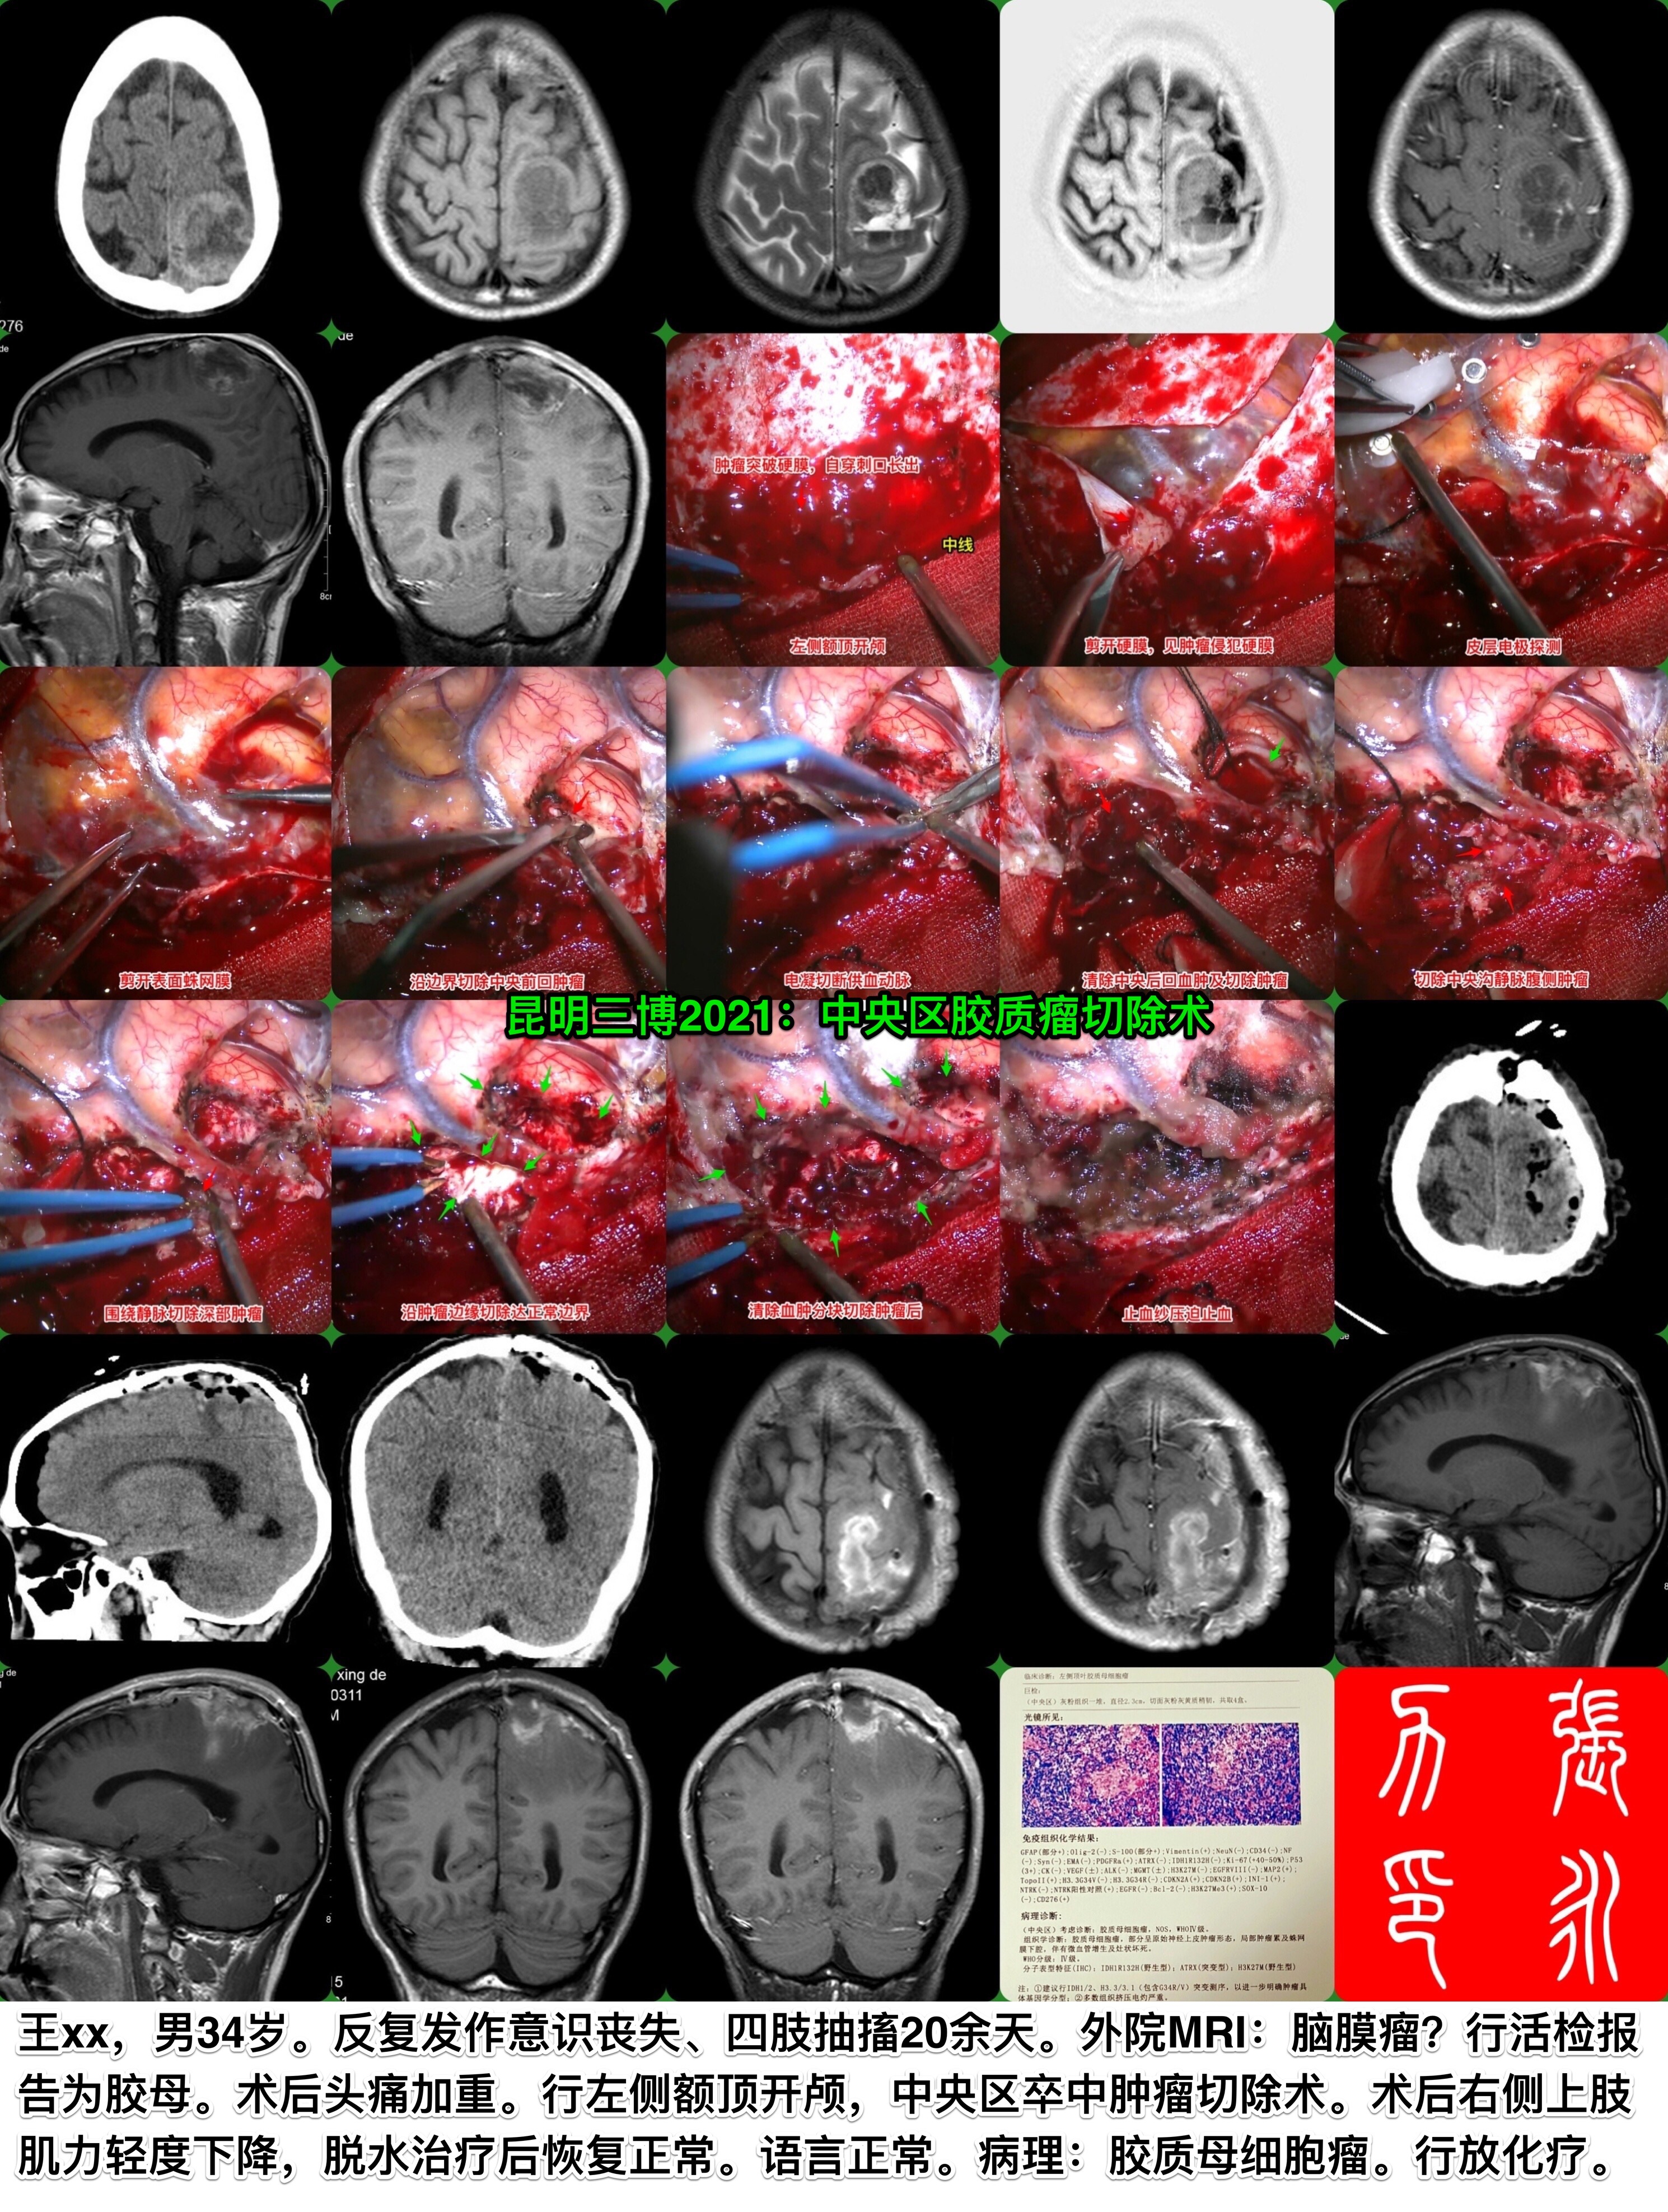

昆明三博2021:中央区胶质瘤切除

张永力

昆明三博脑科医院